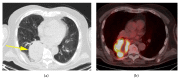

Malignant fibrous histiocytoma (MFH) is one of the most common adult soft tissue sarcomas. MFH is very aggressive and is most often found in the extremities and the retroperitoneum, but it can manifest at other sites. Though the lungs are the most common sites of metastasis, they rarely present there as a primary tumor. Our report describes a rare case of a primary MFH tumor in the lung. Careful diagnostic procedure should be followed to ensure the tumor does not have extrapulmonary origins. Though MFH is highly invasive and deadly, surgical excision of the tumor has been shown to be successful.